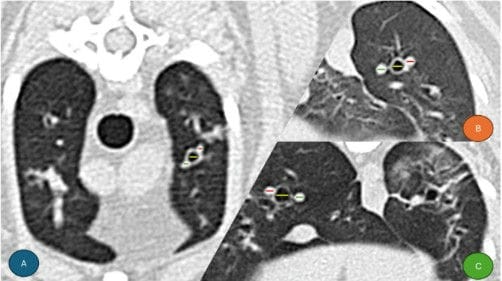

Transverse CT images of the thorax from three seropositive and symptomatic cats with findings compatible with Heartworm-Associated Respiratory Disease (HARD). Colored lines indicate the measurements of the pulmonary artery (red), bronchial lumen (yellow), and pulmonary vein (green), from lateral to medial, respectively. (A) Left cranial lobe (cranial subsegment) at T4–T5. (B) Left caudal lobe at T9–T10. (C) Right caudal lobe at T9–T10.